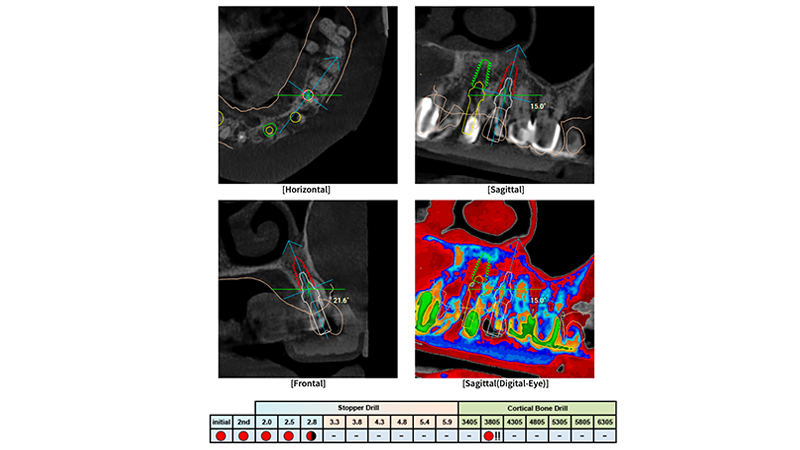

Si è proceduto quindi a pianificare mediante il software R2Gate® la posizione delle fixtures impiantati nei siti che sono stati ritenuti maggiormente favorevoli per poter garantire una stabilità primaria adeguata. Tale procedura è stata semplificata dall’analisi suggerita dal tool “Digital Eye” che ha inoltre suggerito la corretta sequenza di frese da utilizzare per ciascun impianto (Figs. 3, 4, 5)

Pianificazione chirurgica associata a Digital Eye

Fig. 4 - Pianificazione chirurgica associata a Digital Eye, sequenza di frese individualizzata per ciascun sito implantare

La peculiarità di questo sistema è che le guide chirurgiche sono sprovviste di boccole (sleeveless) e sono stampate interamente in resina. Questa è la principale differenza rispetto ad altre sistematiche implantari oggi presenti sul mercato. Inoltre, le guide R2Gate® sono caratterizzate dalla metodica keyless, ossia non è prevista la presenza di alcuno stop o riduttore. La logica alla base di questa metodologia senza boccole e senza riduttori/stop è quella di semplificare le procedure chirurgiche. Infatti, tutte le informazioni relative alla boccola, agli stop per la preparazione del sito osteotomico implantare e ai riduttori sono incluse nella sequenza di frese chirurgiche. Inoltre, il software di pianificazione digitale è dotato di uno strumento chiamato “Digital Eye” che consente di valutare in anticipo la densità ossea in ciascun sito implantare. Su questa base, il chirurgo può modulare la sequenza di fresatura per raggiungere la stabilità primaria in base alla posizione dell'impianto e ai volumi di tessuto disponibili [4-5]. L'obiettivo del presente case report è illustrare la risoluzione di un caso clinico mediante impianti Megagen Anyridge posizionati attraverso l'innovativa sistematica di chirurgia guidata R2Guide (Megagen implants, Daegu, Corea del Sud).